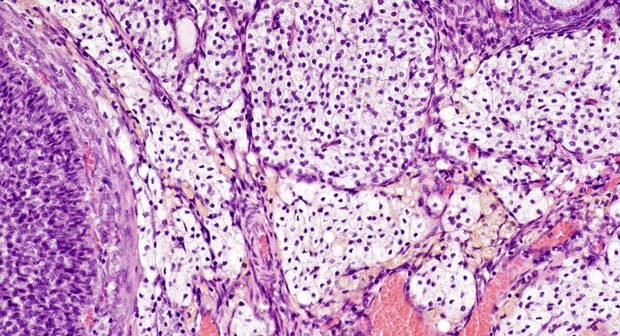

Etichettato per decenni come semplice ‘tessuto connettivo’, l’interstizio era rimasto ‘invisibile’ nella sua complessità a causa dei metodi usati per esaminarlo al microscopio, che lo facevano apparire erroneamente denso e compatto.

La sua vera natura è stata invece osservata per la prima volta grazie ad una nuova tecnica di endomicroscopia confocale laser, che consente di vedere al microscopio i tessuti vivi direttamente dentro il corpo, senza doverli prelevare e poi fissare su un vetrino. Impiegata su alcuni pazienti malati di tumore che dovevano essere sottoposti a chirurgia per rimuovere pancreas e dotto biliare, la tecnica ha permesso di osservare la reale struttura dell’interstizio, che è stato poi riconosciuto anche in tutte le altre parti del corpo sottoposte a continui movimenti e pressioni. Alla luce della sua complessità, l’interstizio si è così meritato la ‘promozione’ ad organo.